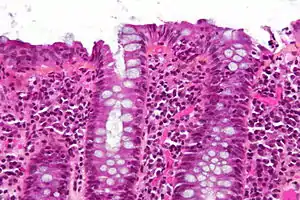

| Micrograph of lymphocytic colitis. HPS stain. | |

The colonoscopy is normal but histology of the mucosal biopsy reveals an accumulation of lymphocytes in the colonic epithelium and connective tissue (lamina propria). Collagenous colitis shares this feature but additionally shows a distinctive thickening of the subepithelial collagen table.[1][2]